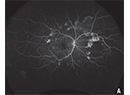

Can RETINAL IMAGING predict progression to DME?

The role of optical coherence tomography, OCT angiography and ultra-widefield fluorescein angiography in identifying risk factors.